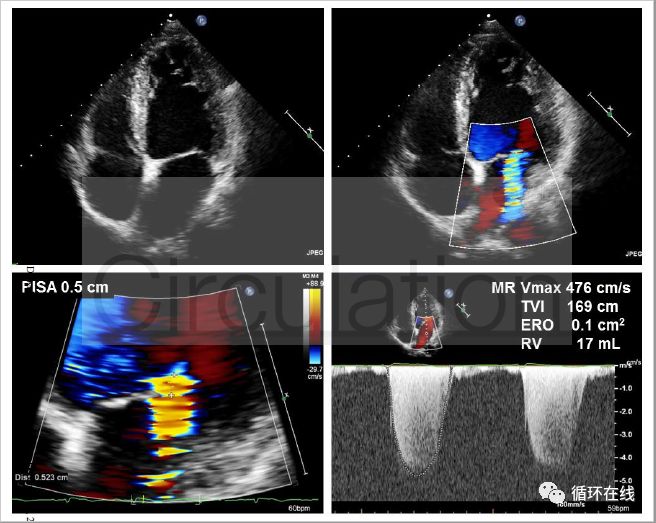

图7(B):使用沙库比曲/缬沙坦治疗12个月后二尖瓣返流改善,EROA显著下降